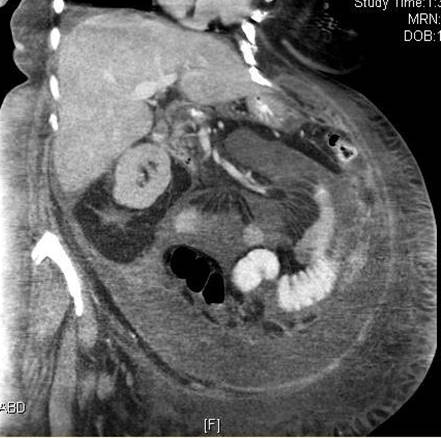

Case Presentation: A 58 year old female with past medical history of microcytic hypochromic anemia and thrombocytosis presented with progressive abdominal distention and pedal edema of 5 months duration. There was no significant history of asbestos exposure.Initial diagnostic paracentesis and peritoneal fluid cytology was negative for malignant cells but showed atypical cells, but tumor markers such as CA 19.9 and CA 125 were elevated. CT scan showed peritoneal nodularity suggestive of peritoneal carcinomatosis and peritoneal biopsy confirmed the diagnosis of peritoneal mesothelioma.

CT scan is crucial to assess the extent of disease and rule out other malignancies. Diagnosis confirmation must be done by tissue biopsy with immunohistological staining.